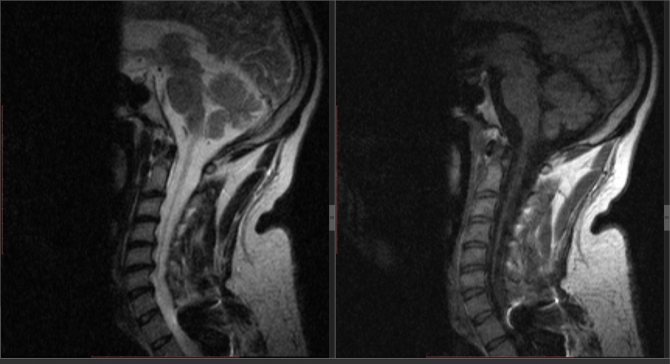

Сирингомиелическая полость представляет собой продолговатую кисту, которая заполнена ликвором и глиальной тканью. Нередко она многокамерная: внутри есть перепончатые (мембранозные) перестенки. По длине и ширине бывает различной, но не больше просвета позвоночного канала.

Киста образуется в сером веществе вдоль цереброспинальной оси (состоит из спинного и головного мозга, синоним: «центральная нервная система»). Чаще полость выявляют внутри мозговой ткани только в 1―2 отделах хребта: шейном, грудном, поясничном. Но трубка может начаться выше первого позвонка «атлант», образоваться ближе к крестцу.

Рекомендуется консультация невролога, магнитно-резонансная томография спинного мозга.

Справка! Подтвердить сирингомиелию может только МРТ либо миелография (рентген или КТ с контрастом).